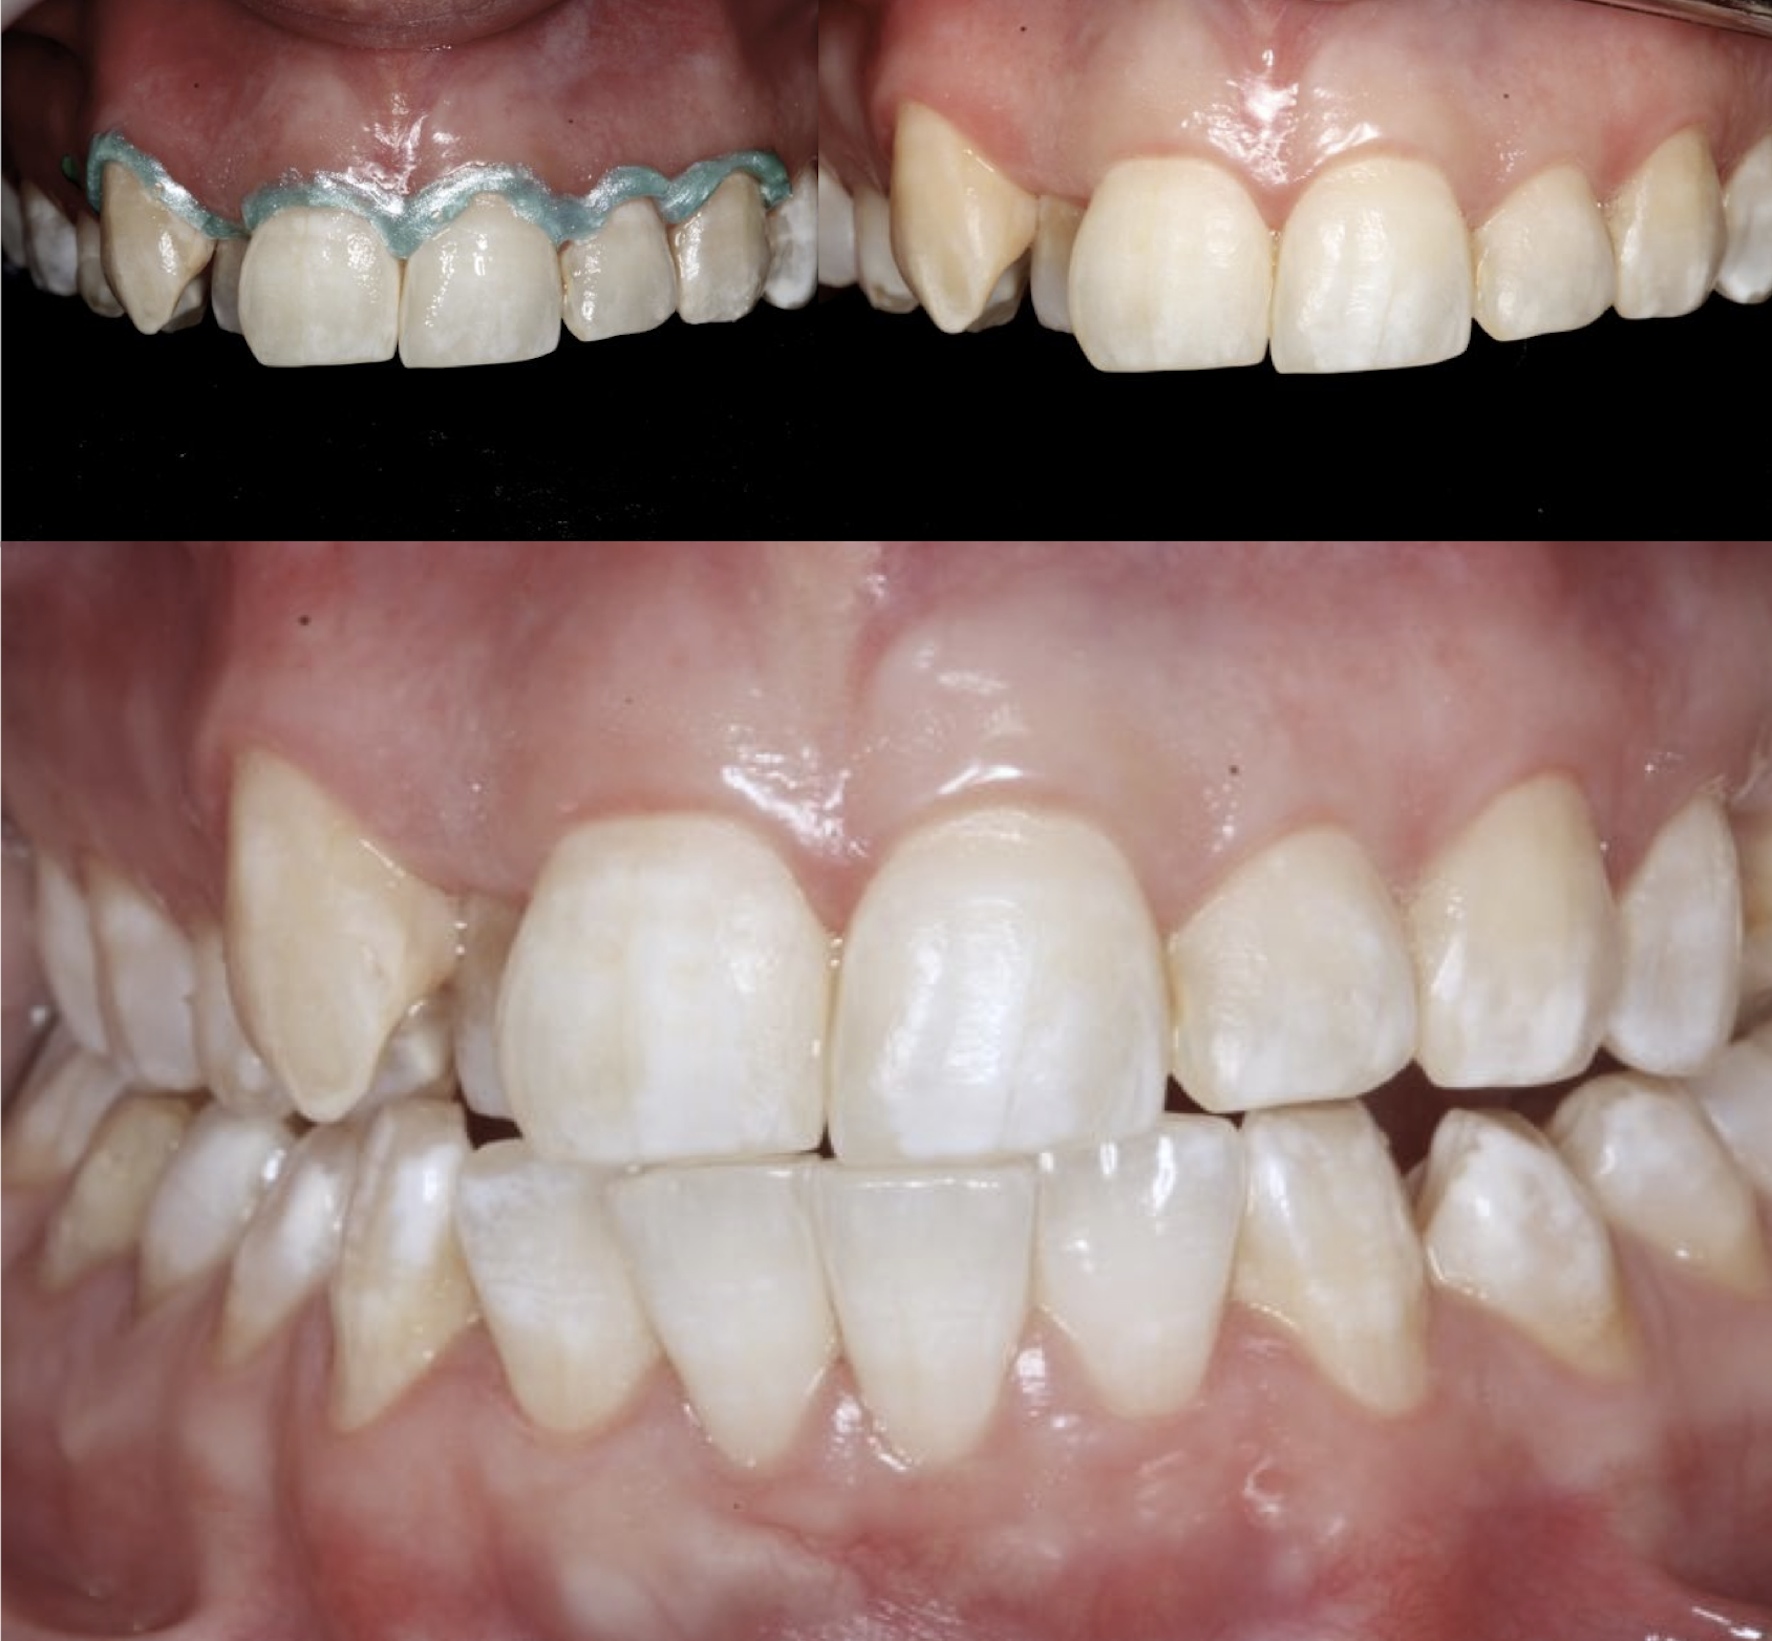

The generalized presence of stain, particularly on anterior teeth, provides an unaesthetic appearance with a negative impact on the patient. The aim of this paper is to report a case of severe chromatic alterations treated with enamel microabrasion associated with infiltration of low-viscosity resin. The intense brownish pigmentation and white spots of fluorosis lose their whitish appearance and look similar to sound enamel. This association of techniques, which might be an alternative to white-masking of intense pigmentation, showed optimal aesthetic results.